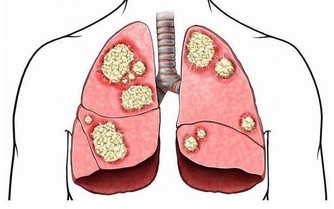

7.清晨浮腫

浮腫是機體細胞外液中水分積聚導致的局部或全身腫脹,與身體很多器官的病變有關。

正常人睡前喝水較多或晚上吃得過鹹,會引起臉部水腫,注意飲食後,多會改善。

但其他部位浮腫要重視,例如眼瞼等疏鬆部位、身體下垂部位浮腫分別代表腎臟和心臟功能出現問題,

若從面部浮腫擴大到全身時,患腎臟疾病的可能性很高,應盡快到醫院檢查,以確定病因。

如果起床一段時間後,眼睛依舊浮腫,就應該到醫院腎內科就診,檢查是否患腎炎等疾病。

若沒有,則可能是腎氣衰弱,除對症服藥外,這類人可在睡前適度按摩眼周,加速眼周血液循環,減輕症狀。